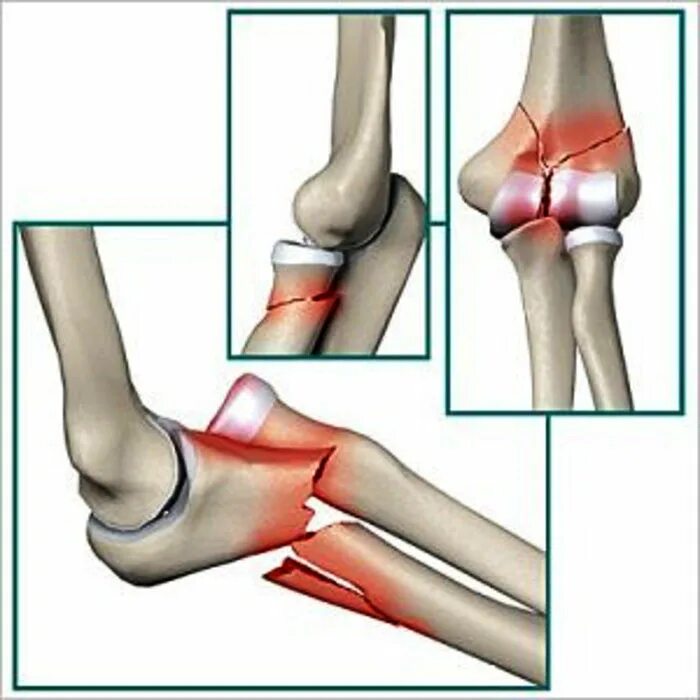

Перелом локтевой